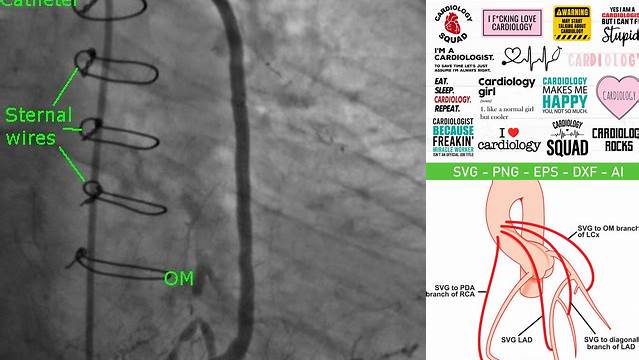

Now, let's talk about OM. In cardiology, OM (Object Model) refers to a structured way of representing data. Imagine organizing all the different parts of a heart – its chambers, valves, blood vessels – into a digital model. That's essentially what an OM does. It's a system that allows us to access and manipulate specific elements of a complex structure, like the heart, in a standardized and logical manner. This is crucial for analyzing the heart's function, identifying abnormalities, and planning interventions. Think of it like a detailed blueprint that can be used to understand how all the pieces fit together and interact. The Object Model provides a hierarchical structure that mirrors the anatomical organization of the heart, enabling clinicians and researchers to navigate through the data with ease. Each object in the model represents a specific component of the heart, such as a valve, chamber, or blood vessel, and is associated with various properties and attributes that describe its characteristics and behavior. This level of detail allows for sophisticated analyses, such as simulating blood flow dynamics, assessing the impact of different interventions, and predicting patient outcomes. Moreover, the OM facilitates the integration of data from multiple sources, such as imaging modalities, physiological measurements, and clinical records, providing a comprehensive view of the patient's cardiac health. This holistic approach is essential for making informed decisions and delivering personalized care. The standardization of data representation through the Object Model also promotes interoperability between different systems and applications, fostering collaboration and knowledge sharing within the cardiology community. This collective effort is driving innovation in cardiac care and ultimately improving the lives of patients with heart disease. The ability to create and manipulate these models programmatically is what makes OM so powerful in modern medical research and clinical practice.

So, why do we need to convert SVG to OM? Well, converting SVG to OM is like translating a picture into a set of instructions. SVGs are great for displaying images, but OMs allow us to interact with the data behind those images. Think of it this way: an SVG is like a map, showing you the roads and landmarks. An OM is like a GPS, letting you plan routes, calculate distances, and get turn-by-turn directions. In cardiology, this means we can take a detailed SVG image of the heart and turn it into a model we can use for analysis, simulation, and even 3D printing. For example, an SVG image might show the shape of a heart valve, but the OM would allow doctors to measure the valve's size, calculate blood flow through it, and even simulate the effects of different treatments. This transformation is crucial for several reasons. First, it enables quantitative analysis, allowing for precise measurements and calculations that are essential for accurate diagnosis and treatment planning. Second, it facilitates the creation of computational models that can simulate the heart's function under various conditions, providing valuable insights into cardiac mechanics and pathophysiology. Third, it supports the development of personalized treatment strategies tailored to the individual patient's anatomy and physiology. By converting SVG images into OMs, cardiologists can leverage advanced computational tools to enhance their understanding of heart disease and improve patient outcomes. This conversion process also plays a critical role in the integration of imaging data with other clinical information, creating a comprehensive and cohesive view of the patient's cardiac health. The ability to manipulate and analyze these models opens doors to new research avenues, paving the way for innovative diagnostic and therapeutic approaches.

The conversion process itself involves a few steps. First, the SVG data is parsed, meaning the code is read and understood by a computer program. Then, the shapes and structures defined in the SVG are mapped to objects in the OM. This might involve identifying contours, surfaces, and volumes that represent different parts of the heart. Finally, these objects are organized into a hierarchical structure that reflects the heart's anatomy. This structured representation is what makes the OM so powerful for analysis and manipulation. Imagine taking apart a complex machine and labeling each part before reassembling it – that's essentially what happens during the conversion process. The software identifies the various components of the heart, such as the ventricles, atria, and valves, and assigns them specific properties and relationships within the Object Model. This detailed mapping allows for accurate measurements and simulations, providing clinicians with a wealth of information to inform their decisions. The parsing stage is crucial, as it involves interpreting the SVG code and translating it into a format that the OM can understand. This often requires sophisticated algorithms to identify and extract the relevant geometric information. Once the shapes and structures are identified, they are converted into objects within the OM, each with its own set of attributes and methods. The hierarchical organization of these objects is essential for maintaining the integrity of the model and ensuring that the relationships between different parts of the heart are accurately represented. This meticulous process transforms a static image into a dynamic, interactive model that can be used for a wide range of applications, from diagnosis and treatment planning to research and education. The conversion process is a blend of art and science, requiring both technical expertise and a deep understanding of cardiac anatomy and physiology.